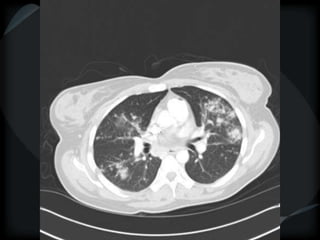

METS

random

Wegener’s

miliary